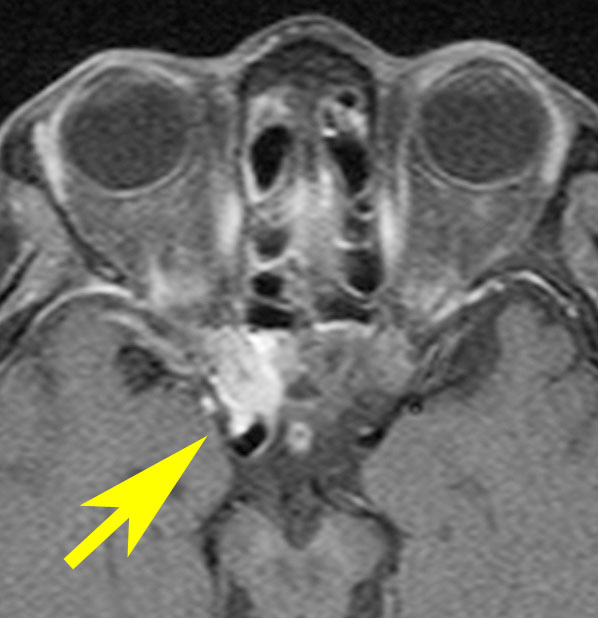

若い女性に偶然発見されたものです。直静脈洞と静脈洞交会の接合部あたりに発生したもので,静脈洞はほぼ閉塞に近い所見でした。しかし,この部分の静脈洞は,テント硬静脈側副路が発達することがあるので,硬膜を含めた積極的な摘出をすることは絶対にできません。もしほんの少しでも流れがある直静脈洞を閉塞させると短時間に脳死になるような脳静脈圧亢進が生じる可能性があるからです。静脈洞内に少し取り残して(右下の矢印)手術を終了しました。手術後には定位放射線治療を行って再増大を防ぎます,